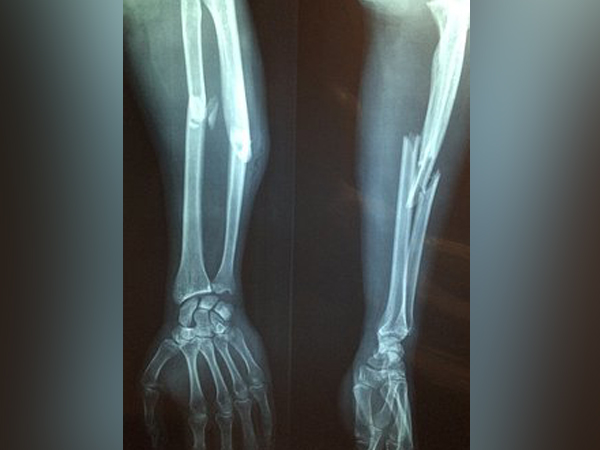

Compartment Syndrome: Causes, Symptoms, Diagnosis And Treatment

When excessive pressure builds up inside an enclosed muscle space in the body, it leads to a condition known as compartment syndrome [1] . This condition usually occurs due to bleeding or swelling after an injury. At times, this condition can be an emergency that would require immediate surgery to prevent permanent injury.

The muscles in the forearm, lower leg and other body areas are surrounded by fibrous bands of tissues. This creates distinct compartments [3] . The fibrous tissue tends to be quite inflexible and so cannot stretch to accommodate swelling in the region (for instance, due to an injury). If left untreated, the muscles and nerves here would fail and eventually die. At times, compartment syndrome can also be chronic, that is because of exertion such as exercise.

Acute compartment syndrome is the most common kind and usually caused due to a broken leg or arm. This condition rapidly develops over hours or days. This condition can also occur without bone fractures and usually occurs due to the following issues [7] :